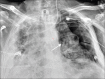

Results: 756 RT-PCR confirmed COVID-19 patients were included in our study who had initial CXR. 510 (67.46%) of our patients with positive initial RT-PCR showed abnormal baseline CXR. The abnormal findings were described as haziness akin to ground glass opacities (GGO) on CT, peripheral opacities, patchy parenchymal opacities and consolidation. Peripheral opacities and lower zone distribution were the commonest pattern of CXR abnormalities with bilateral involvement. The severity of findings on serial CXR and radiographic regression was studied along with follow-up to assess response to treatment. Forty-six patients showed features of acute lung injury (ALI). Complications and new CXR findings were reported for patients who were given ventilator support.